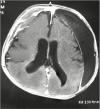

Figures